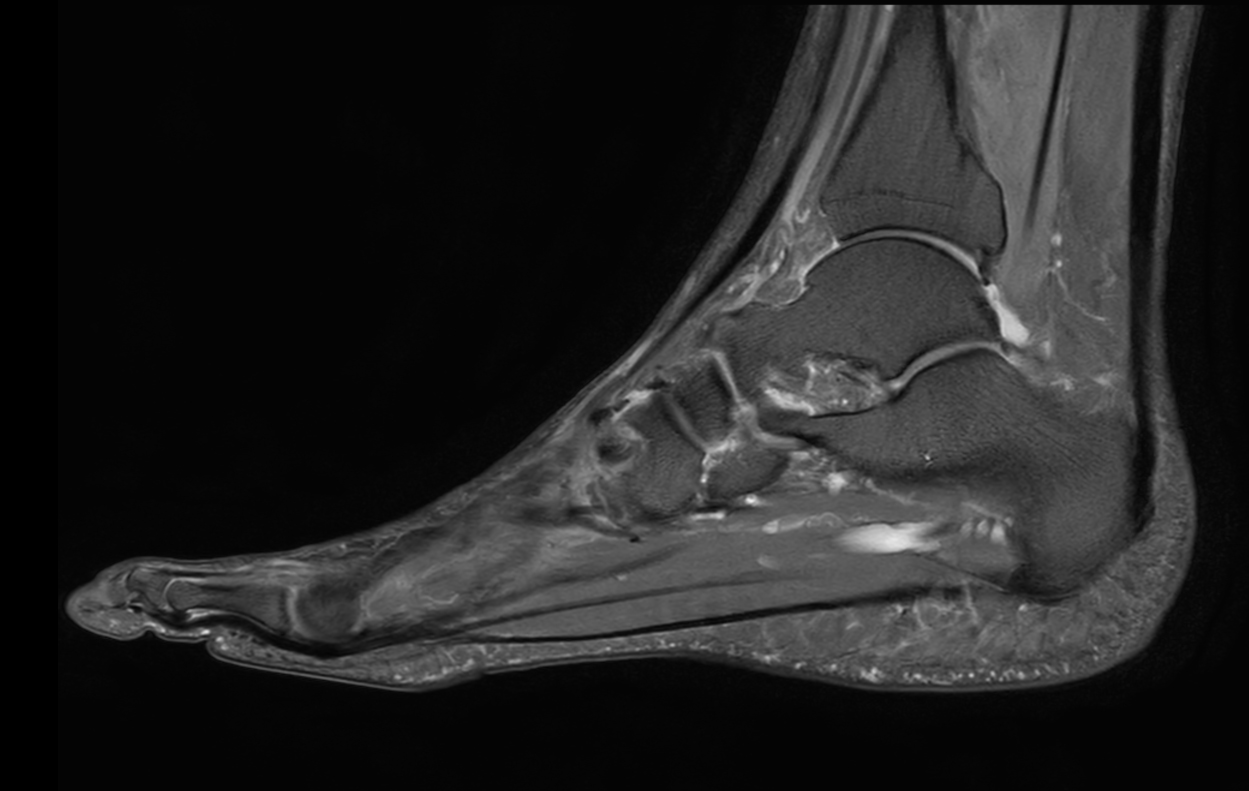

Ankle/Foot imaging post-amputation

Patient with partial amputation of the foot

Sagittal PDw mDIXON XD TSE (Water only)

Sagittal PDw mDIXON XD TSE (In Phase)

Sagittal PDw mDIXON XD TSE (Partial FatSat)